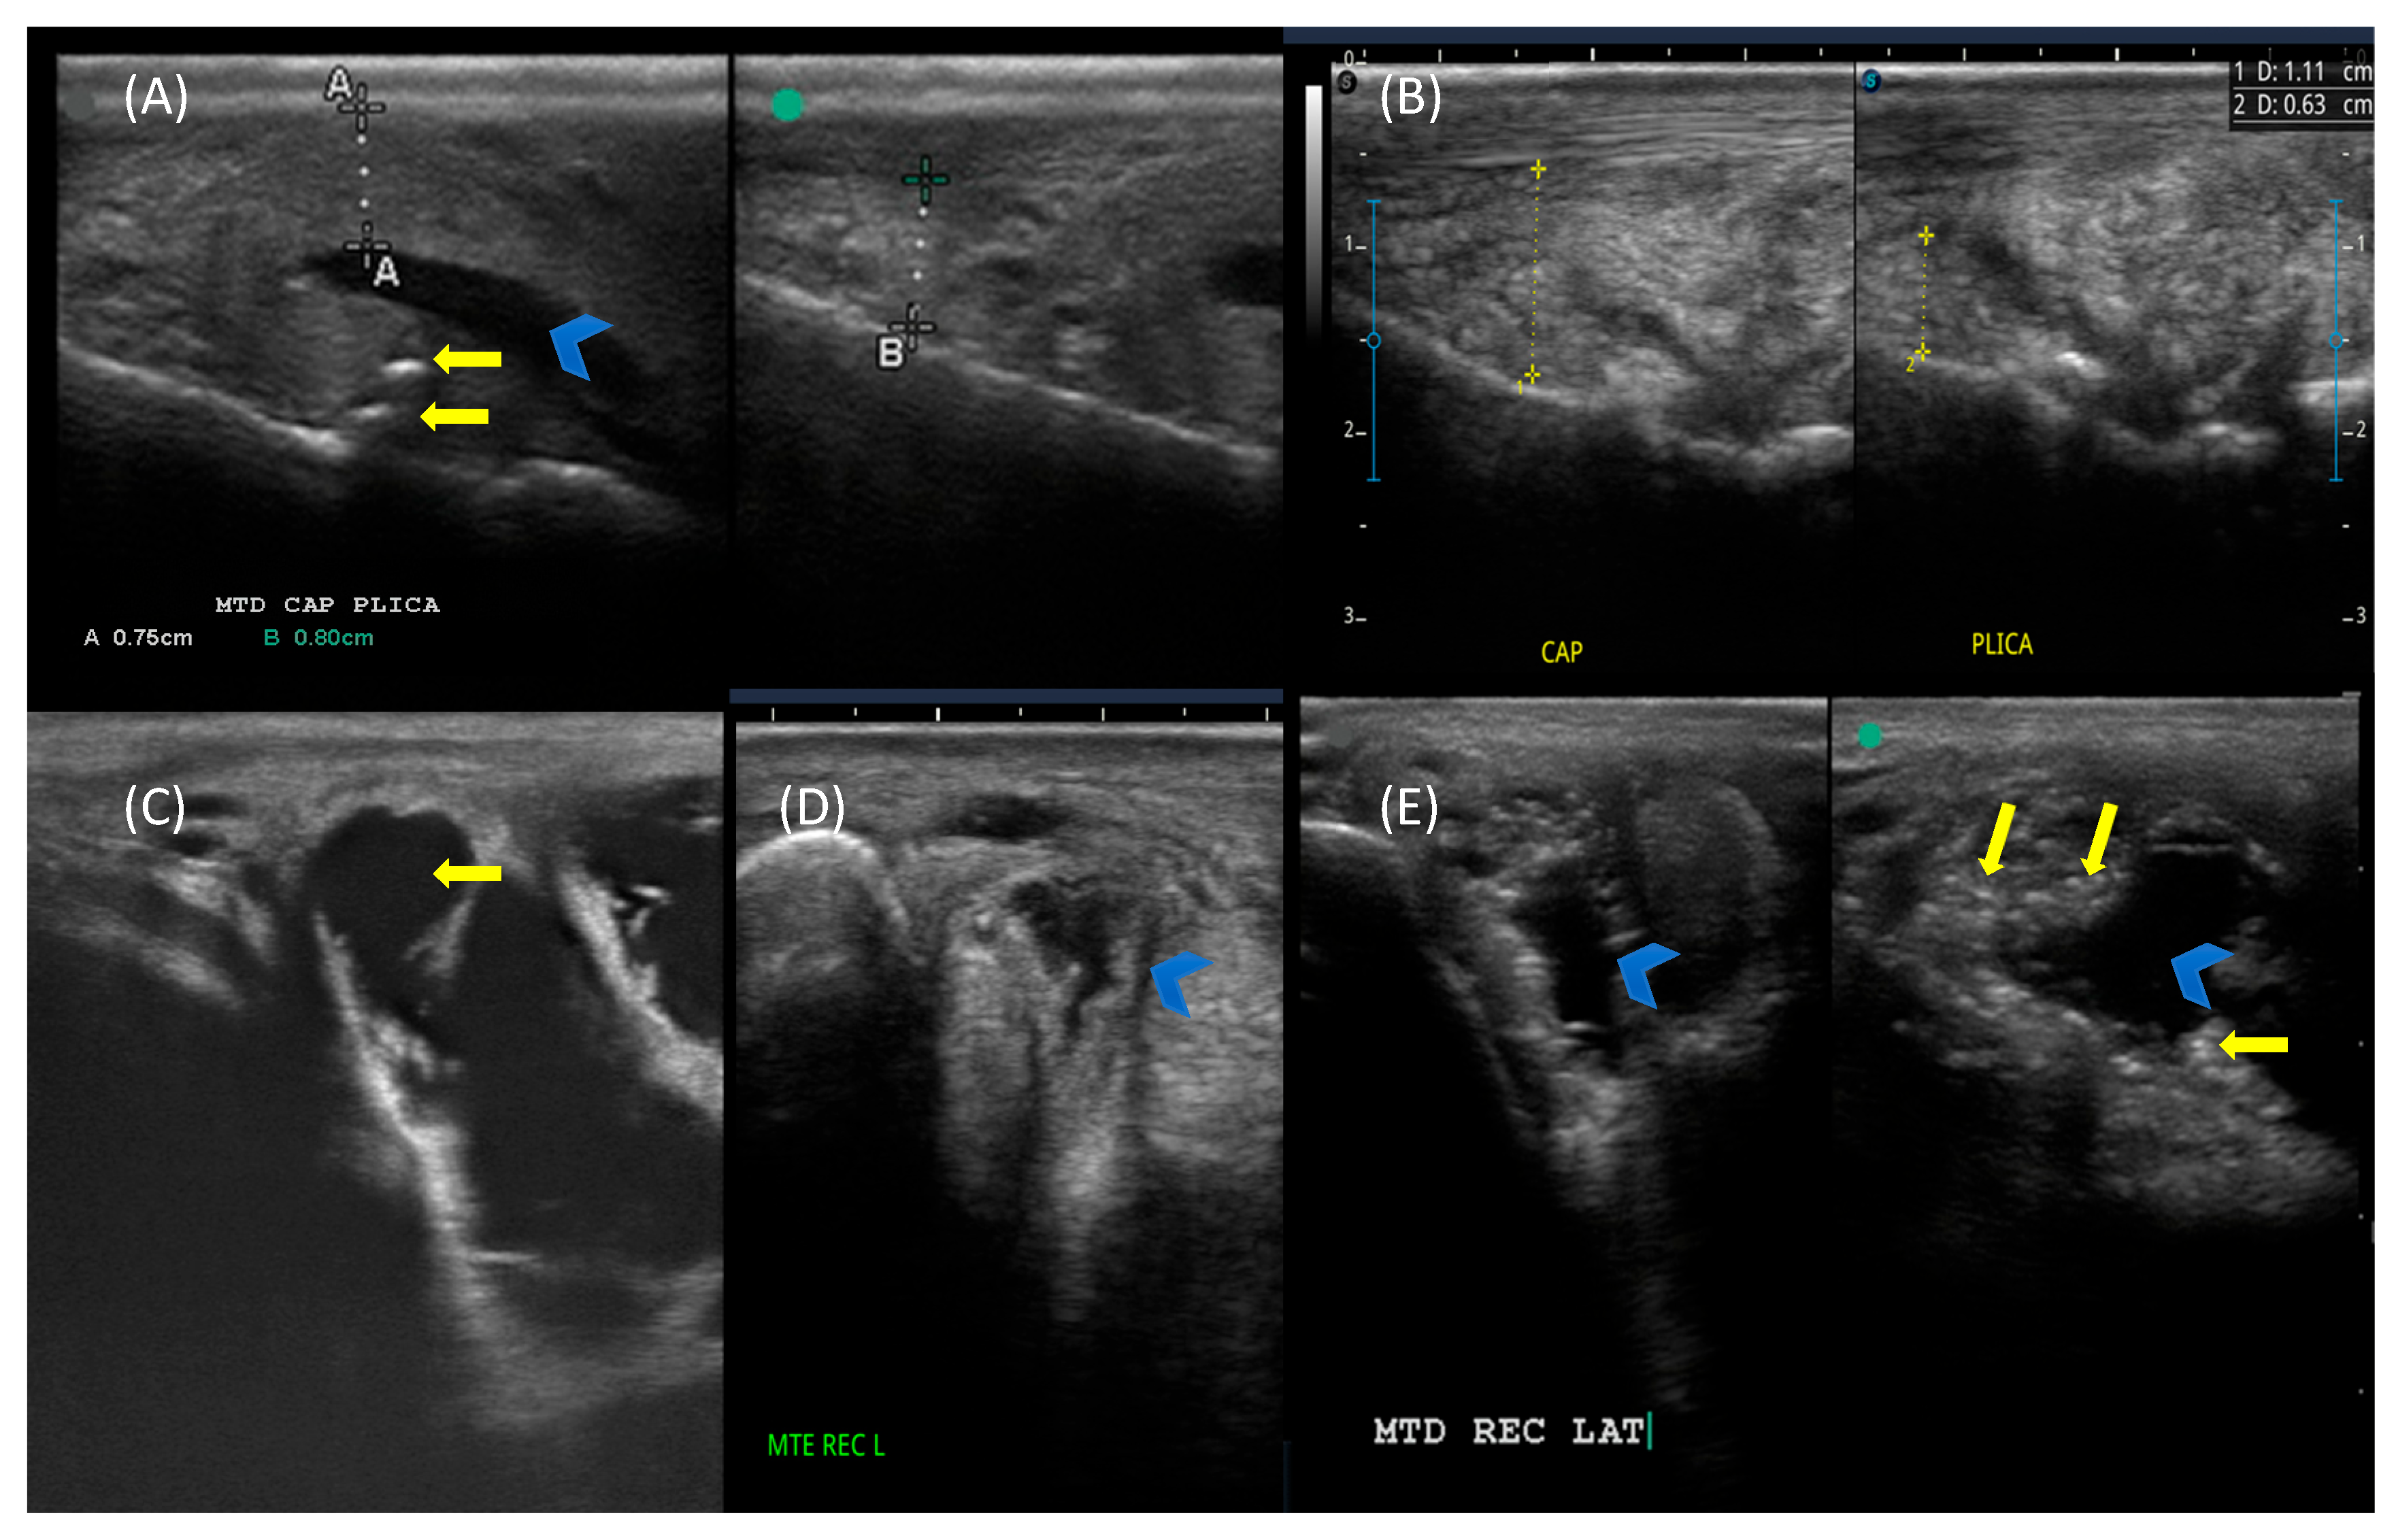

2.5. Ultrasonographic Evaluation

3.4. Ultrasonographic Scoring

4.3. Ultrasonographic Findings